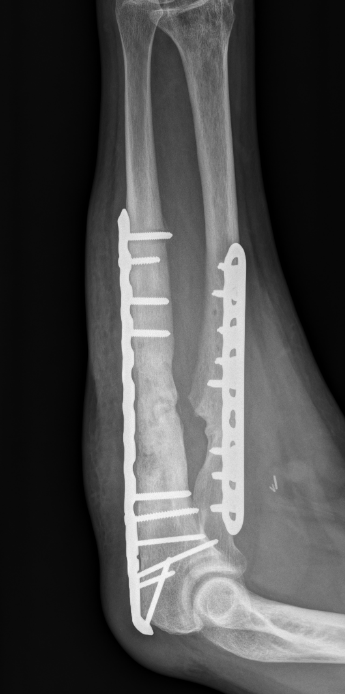

ORIF with DCP plates

Fixation with DCP plates

Nonunion

Incidence

5%

Most common midshaft - reduced blood supply and maximal pronation / supination

Related to

- open fractures

- infection

- poor initial fixation / lack of compression

Options

Revision compression plating + drill intra-medullary canals + autograft

Results

- 35 forearm nonunions treated with revision compression plating and bone grafting

- average defect 2 cm

- 100% union